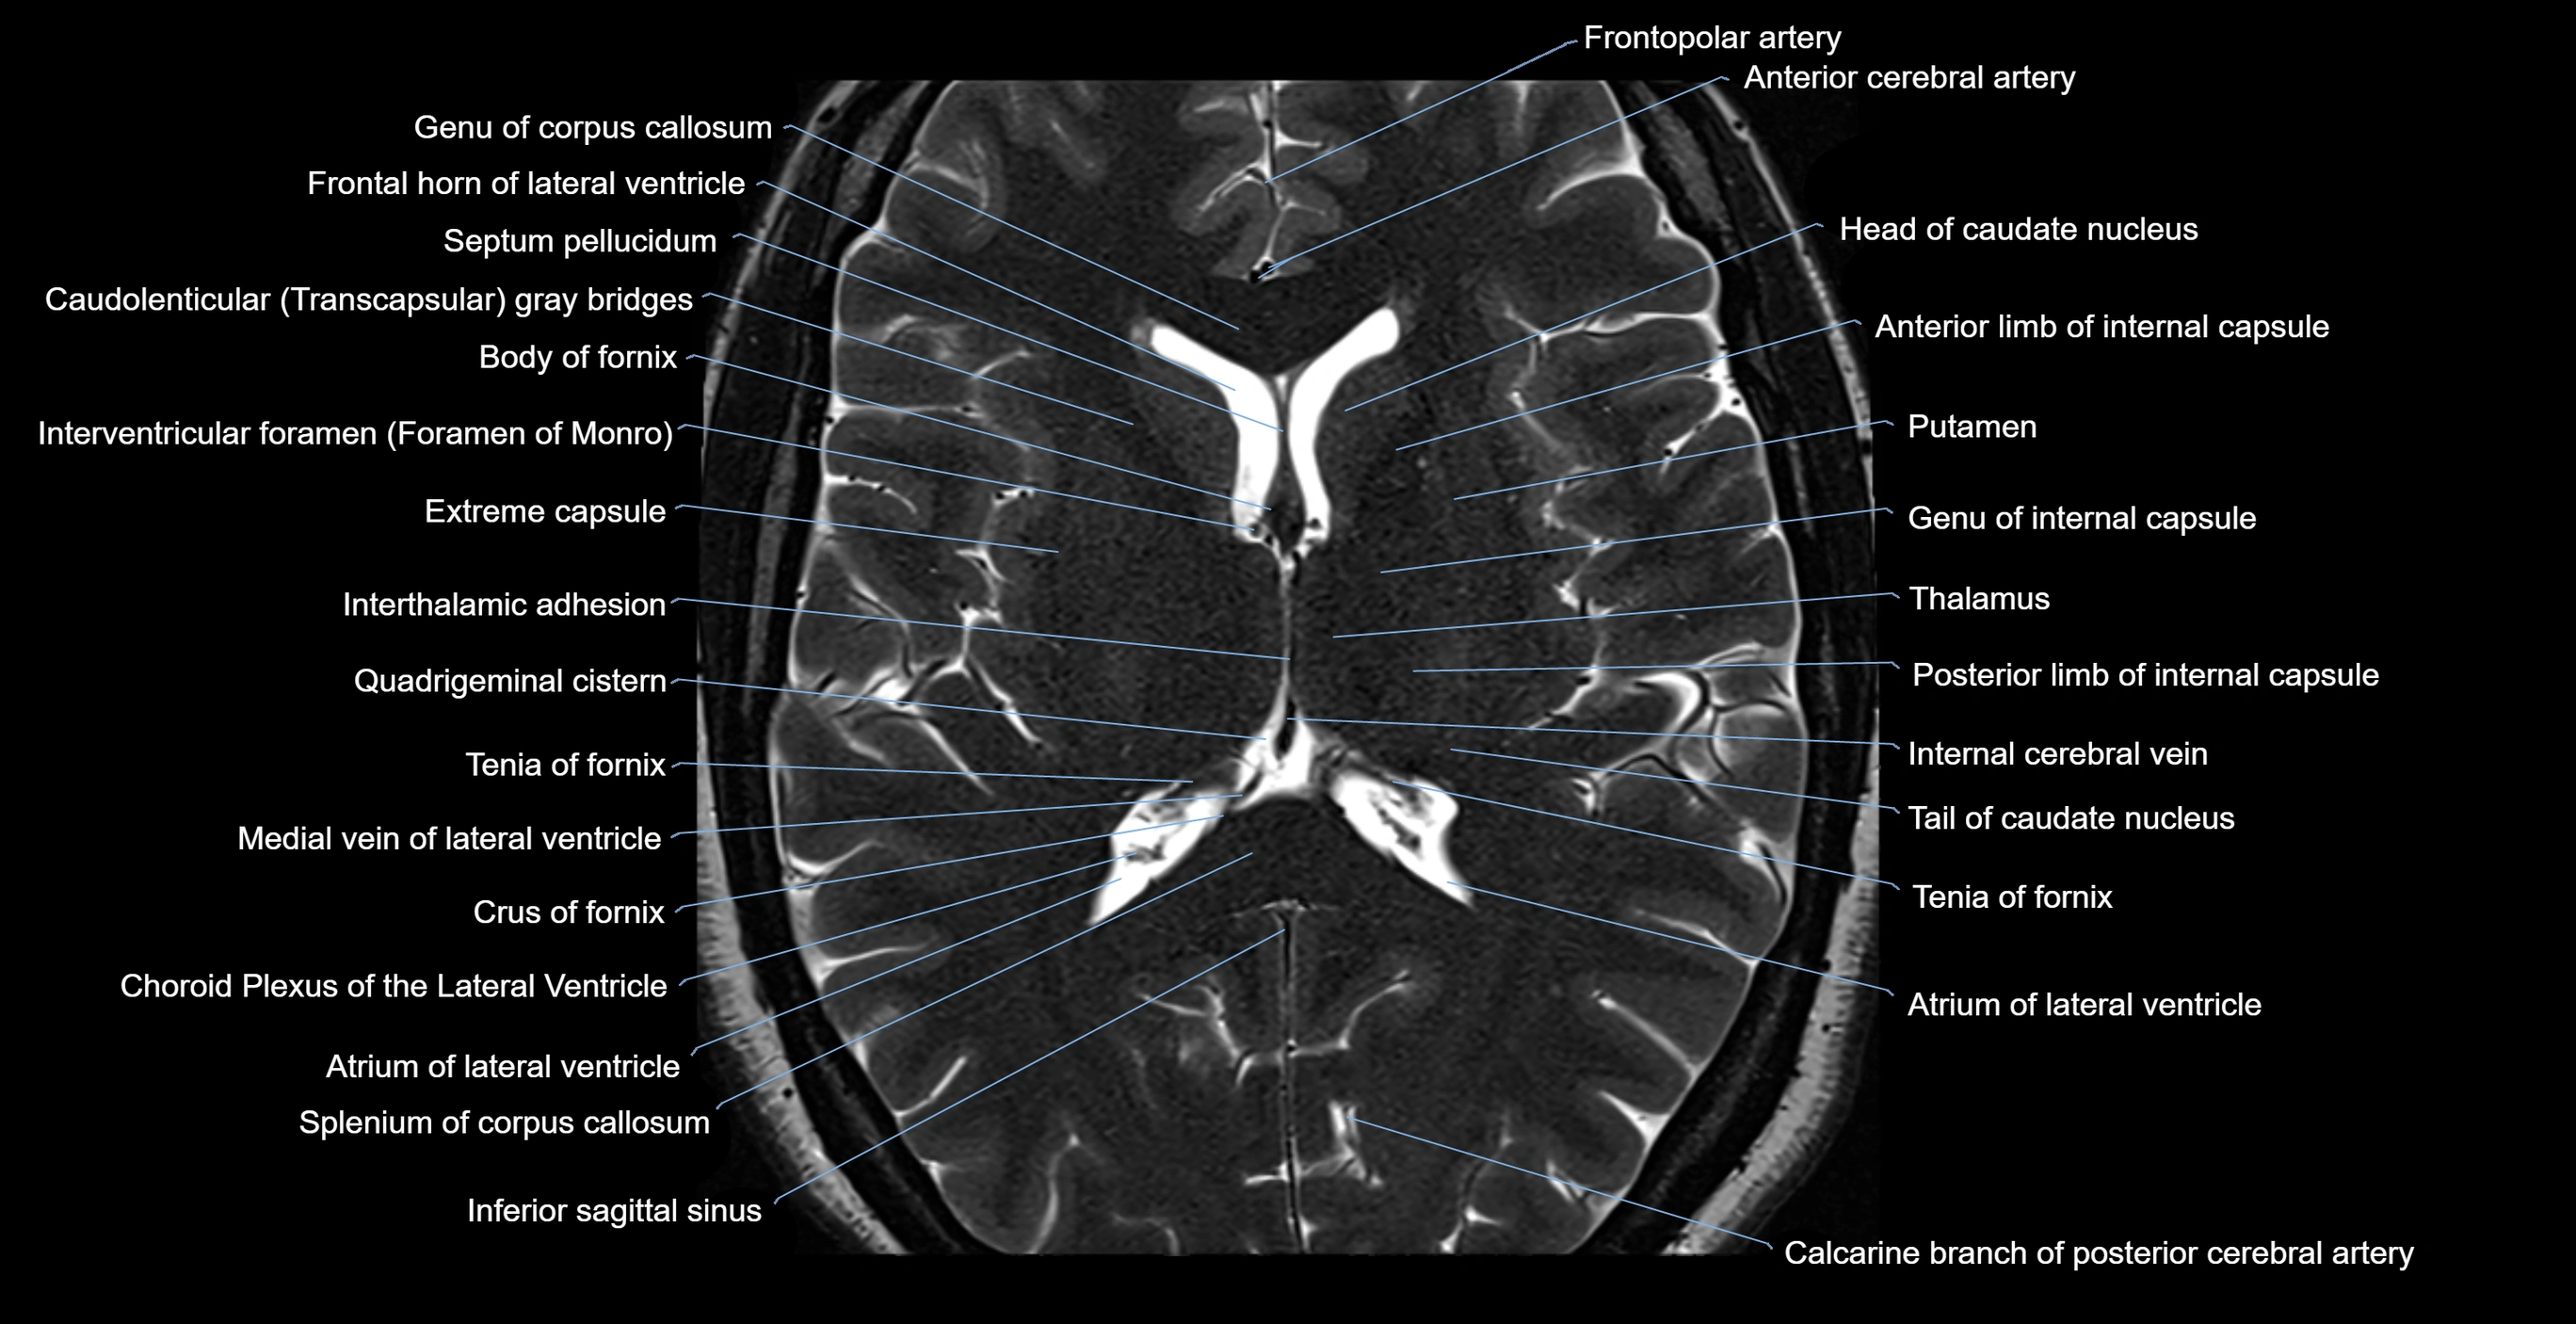

MRI images